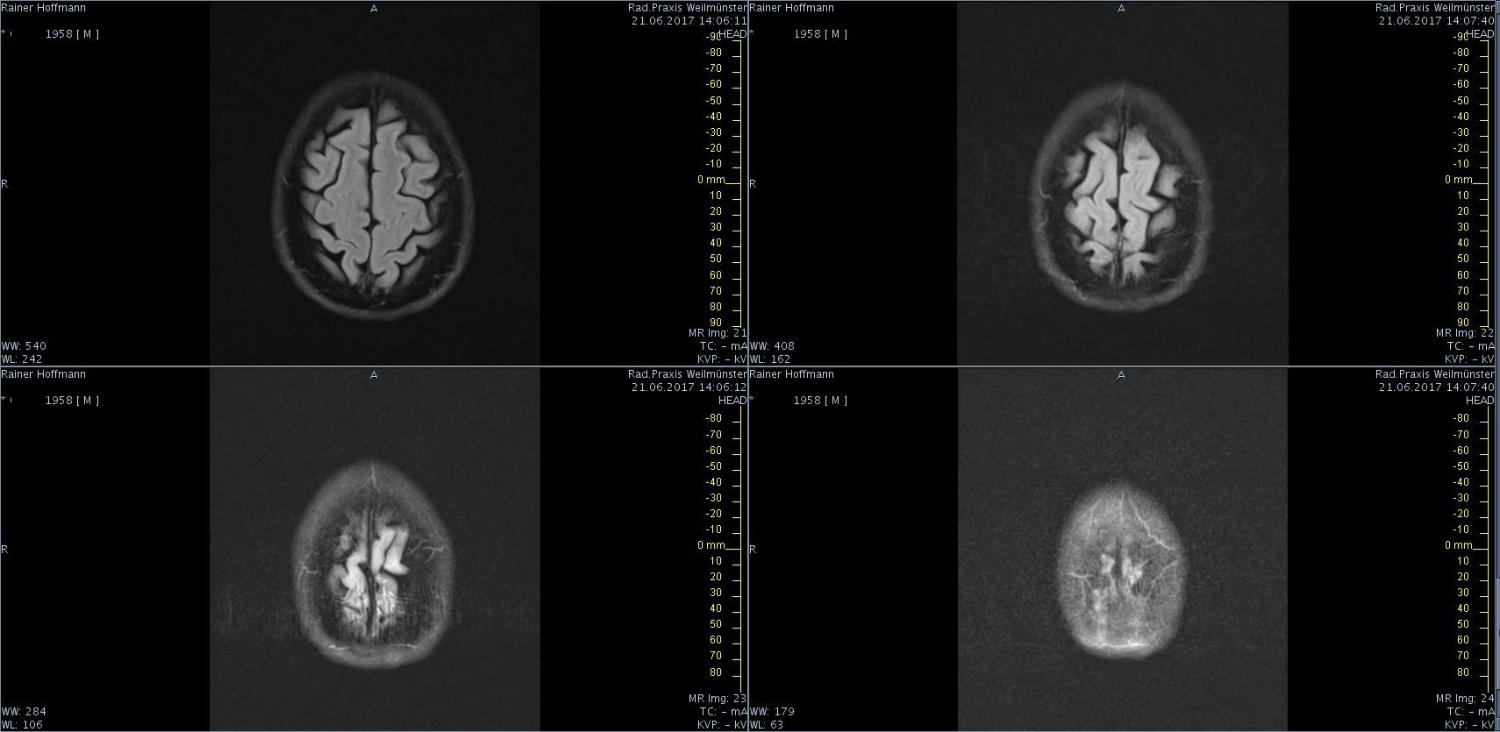

Das ist ja ganz toll, dass Ihr die Seite so schnell gefunden habt. Ich zeige euch jetzt ein ganz, ganz anderes Paßfoto von mir. Es könnte Ähnlichkeiten zu anderen lebenden oder bereits verstorbenen Personen geben. Wenn Ihr das erste Bild oben links anklickt wird es ver- größert dargestellt. Dann kann man mit den Pfeiltasten am unteren Bild- rand durch meinen Kopf blättern. Es gibt nicht viel zu sehen. Vielen Dank an Martina für Ihre Hilfe.

MRT